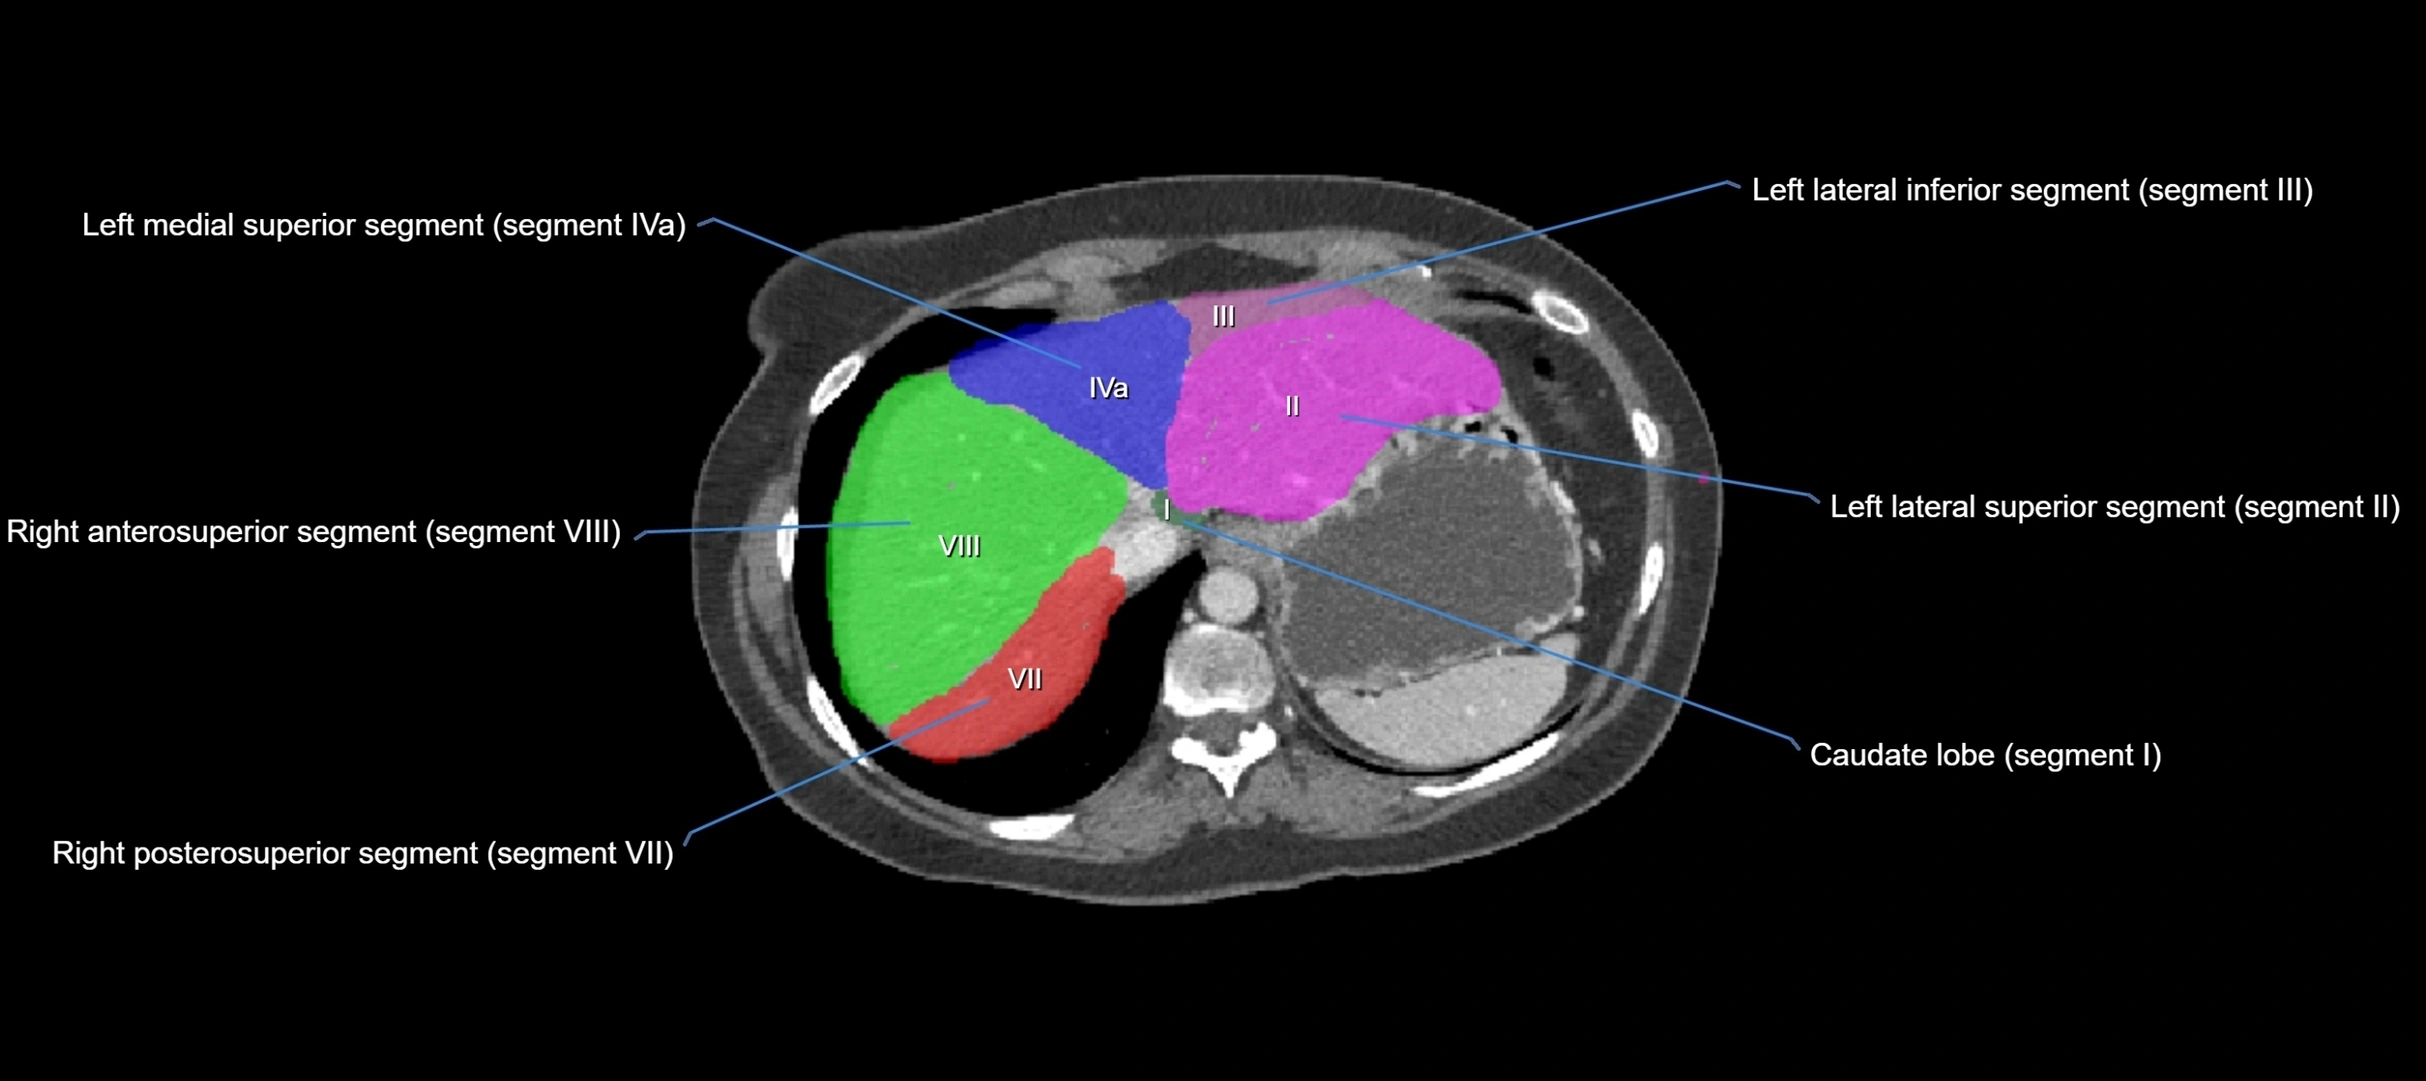

MRI image

image